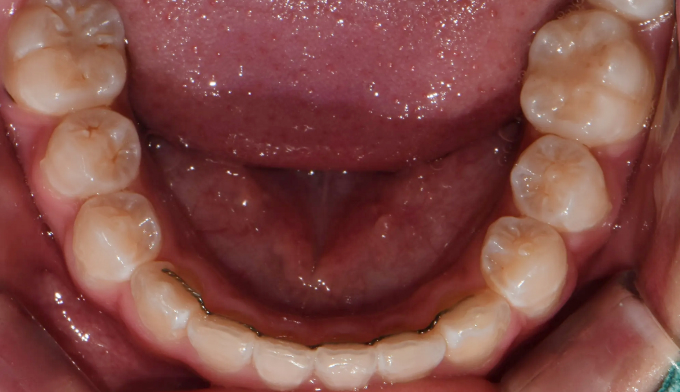

초등학생때 1차교정을 통해 앞니만 배열하였다고 했습니다.

진단해보니 송곳니가 나올 공간이 부족하여 2차교정을 진행하였습니다.

그래도 1차교정을 통해 공간을 어느정도 확보해 놓은것이 2차교정을 더 수월하게 해줍니다.

남아있는 공간을 최대한 활용하여 발치없이 치아를 배열해줍니다.

교정기간은 14개월 소요되었습니다.